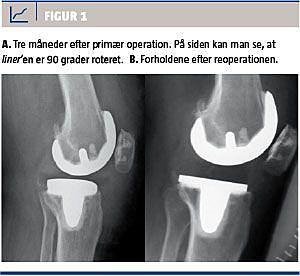

Efter et år, hvor patienten havde fået en ny totalhoftealloplastik og været til yderligere kontroller, bad hun om at få en second opinion. Hun havde stadig smerter og nedsat funktion i venstre knæ. På sygehus D blev der taget nye røntgenbilleder, som viste en 90-graders-rotation af polyætylen-liner’en. Dette gav en forklaring på det langsomme genoptræningsforløb, den indskrænkede bevægelighed og smerterne. Ved gennemgang af de primære postoperative billeder kunne det konstateres, at liner’en allerede på det tidspunkt var roteret 90 grader (Figur 1).

Patienten blev reopereret, og under operationen fandt man liner’en 90 grader roteret og beliggende i det mediale ledkammer. Liner’en blev fjernet, og der var ingen større skader. Der blev isat en ny polyætylen-liner, som var 7 mm tykkere end den første. Tibiaplateauet blev ikke udskiftet. Knæet var stabilt med den nye liner.